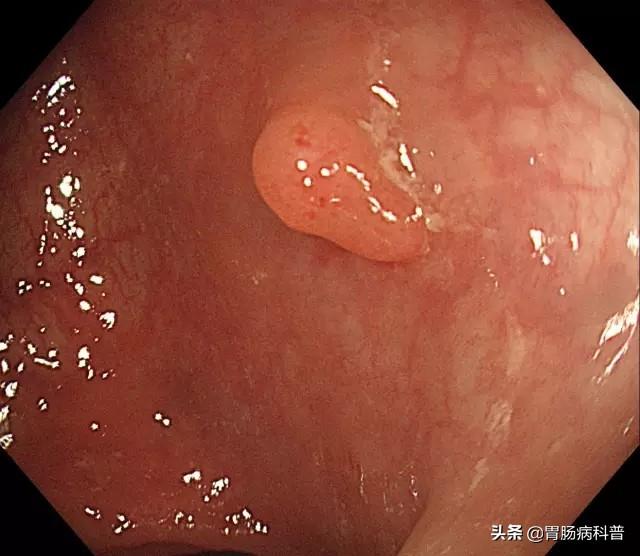

肠息肉就是肠道黏膜上所有隆起性的病变的总称,从结肠黏膜表面突出到肠腔的息肉状病变,通俗地说,就是肠道上长了一些肉疙瘩,人体的整个消化道都可以有息肉生长,其中以结肠和直肠息肉为最多,小肠息肉比较少。在未确定病理性质前均称为结肠息肉。

腺瘤性息肉

息肉的病理学类型包括了肿瘤性和非肿瘤性病变。

炎症性息肉、增生性息肉、错构瘤性息肉等,一般不会癌变,成为非肿瘤性;

腺瘤性息肉择优一定的癌变几率,一般称作腺瘤,或肿瘤性息肉。

炎症性息肉在炎症治愈后可自行消失;腺瘤性息肉一般不会自行消失,有恶变倾向。

值得注意的是,即使是非肿瘤性息肉,只要体积够大,也有恶变倾向。